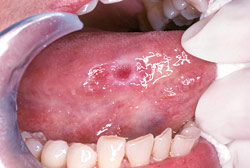

An oral cancer examination is fast and painless. Its objective is to identify small changes in the lining tissues of the mouth, lips, and tongue that may signify the early stages of this type of cancer. The Baltimore cancer screening is primarily a visual and tactile (touch) examination. If any abnormalities are noted, a small tissue sample can be retrieved for further testing in a laboratory.

A thorough screening for oral cancer is part of your routine dental checkup — another reason why you should be examined regularly. The screening includes a visual assessment of your lips, tongue, and the inside of your mouth, including a check for red or white patches or unusual sores. You may be palpated (pressed with fingers) to detect the presence of lumps and swellings, and your tongue may be gently pulled aside for an even better view. A special light, dye, or other procedure may also be used to help check any suspect areas. If anything appears to be out of the ordinary, a biopsy can be easily performed.

If you notice abnormal sores or color changes in the tissue of your mouth, lips and tongue, they may be a symptom of oral cancer — most, however, are completely benign. But sores or other unusual changes that haven’t gone away by themselves after 2-3 weeks should be examined. Remember, the only way to accurately diagnose oral cancer is through a laboratory report. Early diagnosis, aided by thorough screenings at your regular dental checkups, is one of the best defenses against oral cancer.